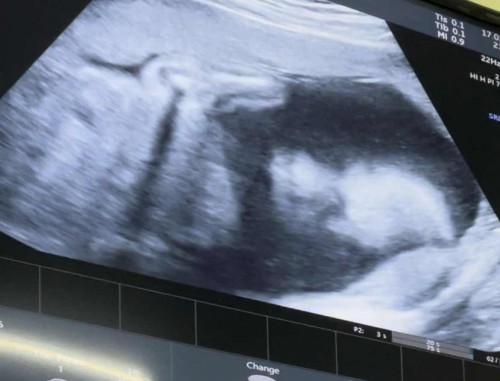

ของเราน้องได้25wแล้ว ตัวใหญ่มากคุณแม่ต้องคุมอาหารแบบสุดๆเลยค่ะ วัยนี้น้องใบหน้าสมบูรณ์มากๆแล้ว แม่ๆเริ่มเห็นหน้าน้องกันรึยังคะ?? ปล.ผมชอบโชว์แบบนี้ตั้งแต่12wแล้วงับ

บ้านนี้ซาวด์ล่าสุด22w น้องนอนคว่ำเอาหน้ามุดไปแบบไม่ให้เห็นเลยค่ะ🤣